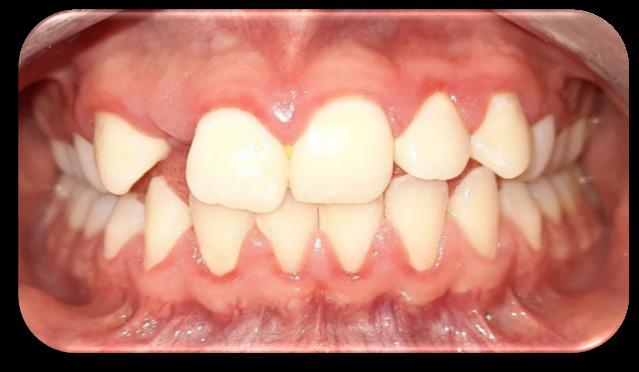

Inclusión dentaria por un odontoma compuesto

Dental inclusion by a compound odontoma

Javier Burgos, Francis Argandoña, Gabriela Adriana Lara...................................................................107-115